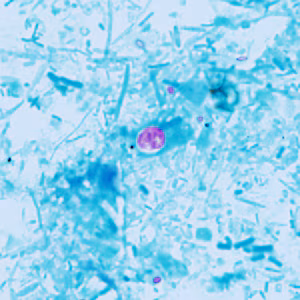

2015 DPDx Case Studies

DPDx Case Studies – 2015

DPDx is an educational resource designed for health professionals and laboratory scientists. For an overview including prevention, control, and treatment visit www.cdc.gov/parasites/.